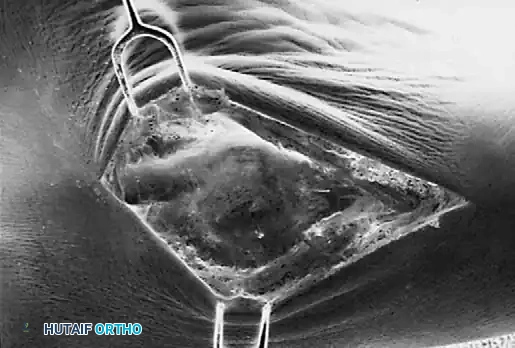

جراحة إزالة التحام العقب والزورقي

في حالة التحام العقب والزورقي، يعتبر الاستئصال الجراحي للجسر العظمي هو الخيار المفضل، خاصة لدى الأطفال والمراهقين الذين لا يعانون من خشونة في المفاصل.

يقوم الجراح بإزالة الجسر العظمي بالكامل لضمان عدم عودته. ولمنع تكوّن العظم مرة أخرى في نفس المكان، يتم وضع نسيج عازل في الفراغ الناتج، مثل جزء من عضلة مجاورة (Extensor digitorum brevis) أو نسيج دهني، أو استخدام الشمع الطبي. أثبتت الدراسات أن هذه الجراحة تنجح بنسبة عالية في تخفيف الألم واستعادة جزء كبير من حركة المفصل.